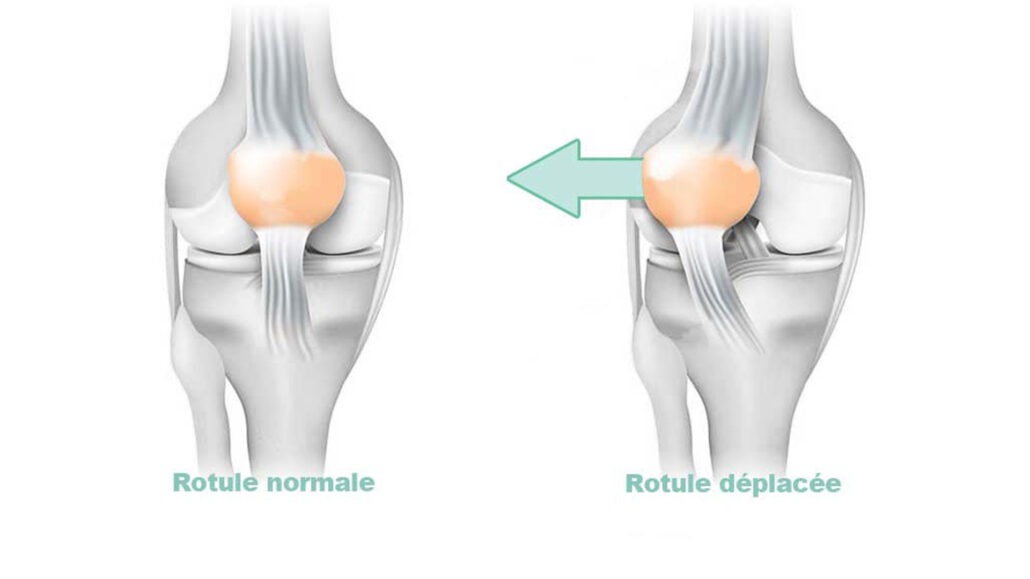

Instabilité Rotulienne

L’instabilité rotulienne est un dysfonctionnement où la rotule ne glisse pas correctement dans la gorge du fémur, ce qui provoque des douleurs, une sensation de déboîtement, voire des luxations complètes. Elle est souvent due à des facteurs anatomiques comme une gorge fémorale trop plate (dysplasie) ou un mauvais alignement des tendons. Le traitement est d’abord médical et repose principalement sur la kinésithérapie, qui est souvent suffisante. La chirurgie n’est envisagée qu’en cas de luxations à répétition et vise à corriger les anomalies pour stabiliser la rotule. La réussite de la prise en charge, surtout après une opération, dépend de manière cruciale d’une rééducation bien menée.